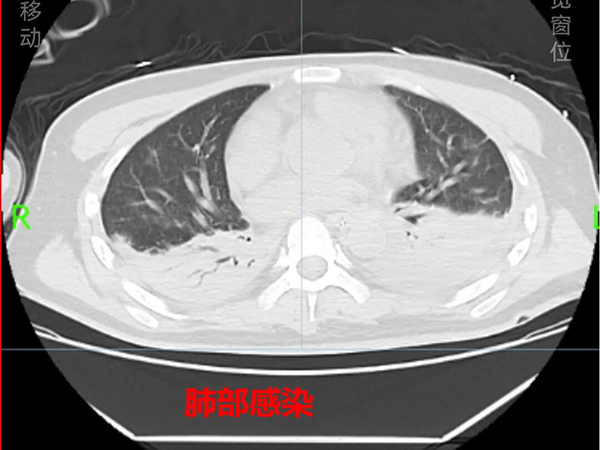

入院时,小周气管、胃管、尿管多重插管,病情复杂危重,不容乐观——呼吸心跳骤停后,虽经3分钟紧急复苏成功,但生命体征不稳,仍处于深度昏迷状态,对光反应迟钝,多项检验指标异常,影像结果提示左侧额颞叶多灶性脑出血,蛛网膜下腔少许出血,颞枕部硬膜下血肿,脑室系统积血,脑中线右偏,双肺坠积改变,还伴有中枢性呼吸衰竭、电解质紊乱和低蛋白血症,预后不佳。

多重插管尚未拔除,肺部感染、脑室积血仍需对症处理,长期卧床导致的肌力下降,让他连抬手、起坐这类基础动作都难以自主完成。

神经内科、神经外科与康复医学科接过救治的“接力棒”:一方面,予以脑保护、抗感染、抗癫痫、止咳化痰、营养支持等对症治疗;另一方面,采取渐进式呼吸肌训练、咳嗽排痰训练、肢体锻炼等综合训练。经过1个多月的系统治疗与精心护理,小周顺利拔除了气管插管和尿管,恢复了自主呼吸和言语功能,复查显示其颅内积血已基本吸收,脑中线复位,肺部感染也得到有效控制,并于1月28日顺利出院。